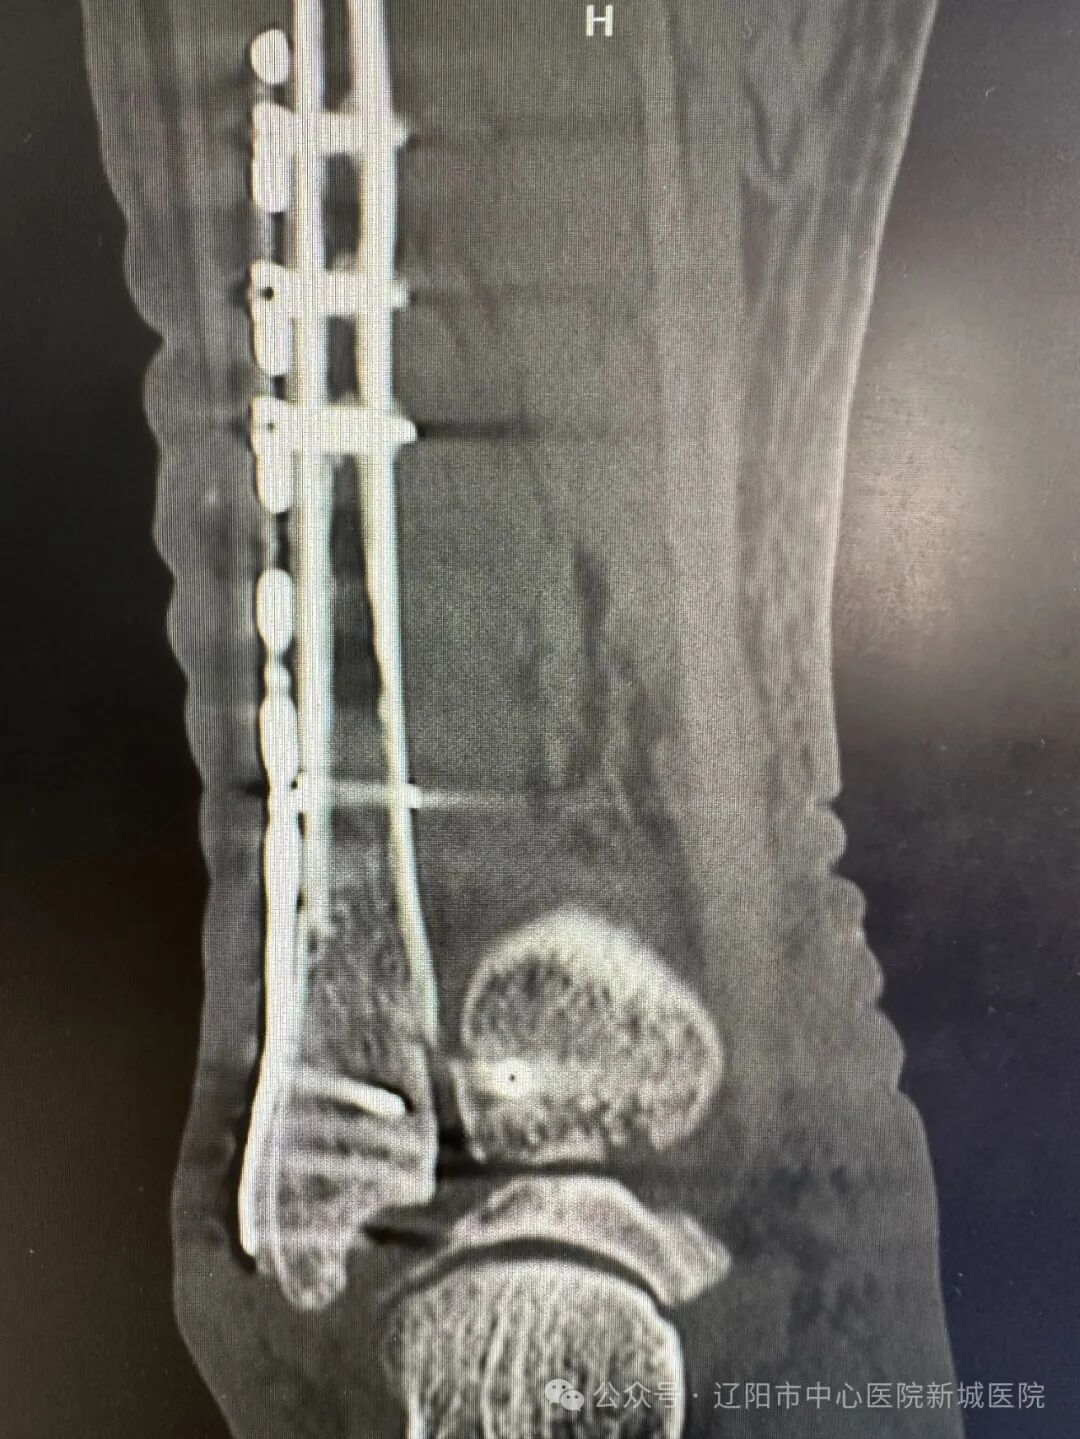

在完成術(shù)前準(zhǔn)備后,按照擬定了手術(shù)計劃,姚醫(yī)生與團(tuán)隊醫(yī)生們?yōu)楸∨渴┬辛?ldquo;踝關(guān)節(jié)骨折切開復(fù)位內(nèi)固定術(shù)”。術(shù)中所見骨折位置和預(yù)判一致,三踝骨折。在C型臂X線機的輔助下,完成了外踝固定、后踝固定、內(nèi)踝固定,螺釘和鋼板位置固定穩(wěn)固,一次復(fù)位成功,手術(shù)順利完成。